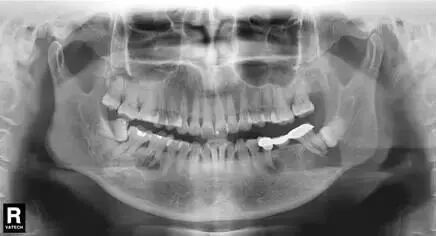

牙医警示 “看牙”第一步,为什么要拍片?

牙医要警惕!拔除松动牙

一定要拍一个全景片

因此,如果牙齿出了问题,口腔医生就需要有“透视”功能的X线片来检查。通过x线片不仅能了解牙齿本身的病变情况,还可以了解牙根下有没有囊肿、周围骨头有没有吸收以及牙槽骨内是否有埋伏牙、多生牙等。依据X线片综合分析,可以提高齿科医生诊断治疗牙齿的准确性和成功率。

常见的牙科放射检查包括曲面体层片( 全景片 )、小牙片、头颅正侧位片、全头颅 CT、锥形束 CT( CBCT )等。由于牙齿下部隐藏在牙槽骨中,口腔医生要了解牙齿的整体情况就需要拍摄全景片;

这里要特别强调一下全景片,建议每个人一生要至少为自己的牙齿拍一张全景片——

通过全景片不仅能了解“牙齿”本身的病变情况,还可以了解“牙根”下有没有囊肿、周围骨头有没有吸收 以及 牙槽骨内是否有“埋伏牙”、“多生牙”等 其它外观不能看见的病灶。